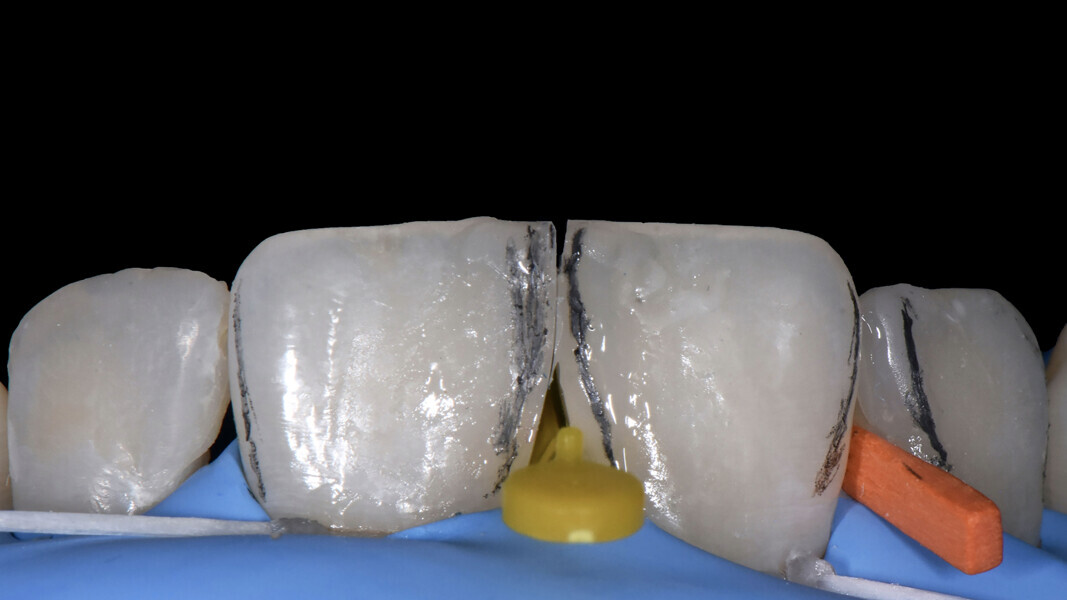

Fig. 10: Simultaneous use of the two matrices (placed vertically).

Fig. 11: Construction of the mesial wall of tooth #21.

Closure of the diastema between teeth #11 and 21 The operative steps chosen to close the space between teeth #11 and 21 were carried out using a technique we adapted involving the simultaneous use of two appropriate sectional matrices (Fig. 10) applied sequentially as described next. This was done drawing inspiration from scientific work aiming to restore, in a single clinical session, the natural smile line of patients with periodontal disease8 or to manage the matrices in a versatile manner.9

First of all, the first metal sectional matrix (thickness of 60 µm) was positioned vertically and fixed with a wedge (Ena Matrix). To obtain a clinical preview of the contact point of the central incisors,10 we then added a second matrix, again in a vertical position, with the intention of defining the emergence profile when performing the cervical restoration. It acts passively on the wedge and pushes it against the interdental papilla. Having stabilised the wedge and matrix system, the first layer of sculptable composite (Admira Fusion, Shade A2; VOCO) was applied to the mesiovestibular wall of tooth #11 using the median landmark created by the physical contact generated between the two matrices. Not too much material should be applied in the vestibular-palatal direction. This system offers the advantage that, once a matrix has been removed, the special wedge can be left in place for haemostatic purposes ready for the insertion of another matrix of the same system. The sectional matrix was removed from the wall of tooth #11 while maintaining the previously achieved anatomical limits (Fig. 11). We then applied a composite increment to the mesial wall of tooth #21, as here the matrix was still in place.11